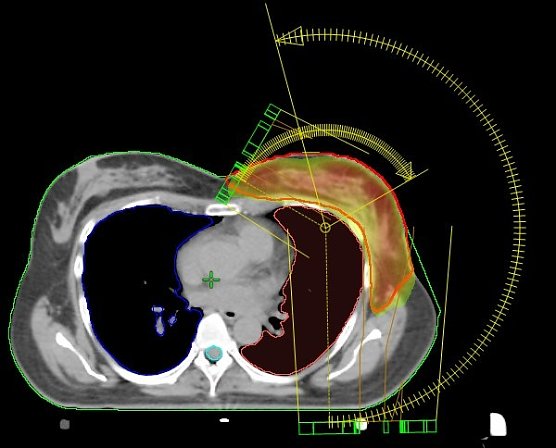

VMAT-Bewegungsbestrahlungstechnik (Foto: Südharz Klinikum) VMAT-Bewegungsbestrahlungstechnik (Foto: Südharz Klinikum)

Einzigartig in Nordhausen: VMAT-Bewegungsbestrahlungstechnik mit 2 Bögen (Nordhäuser Standardtechnik); der Hochdosisbereich erfasst ausschließlich das Zielvolumen und die umgebenden Risikoorgane werden geschont.